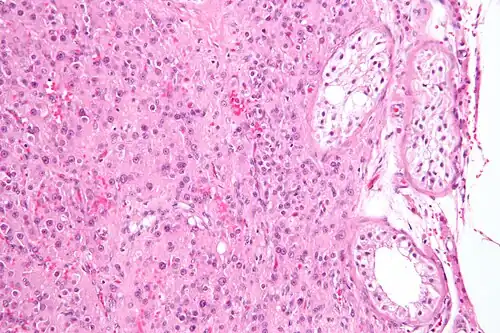

Micrograph showing a cluster of Leydig cells (center of image). H&E stain.

Leydig cells, also known as interstitial cells of the testes and interstitial cells of Leydig, are found adjacent to the seminiferous tubules in the testicle and produce testosterone in the presence of luteinizing hormone (LH).[1][2] They are polyhedral in shape and have a large, prominent nucleus, an eosinophilic cytoplasm, and numerous lipid-filled vesicles.[3] Males have two types of Leydig cells that appear in two distinct stages of development: the fetal type and the adult type.[4]

The mammalian Leydig cell is a polyhedral epithelioid cell with a single eccentrically located ovoid nucleus. The nucleus contains one to three prominent nucleoli and large amounts of dark-staining peripheral heterochromatin. The acidophilic cytoplasm usually contains numerous membrane-bound lipid droplets and large amounts of smooth endoplasmic reticulum (SER).[5] Besides the abundance of SER with scattered patches of rough endoplasmic reticulum, several mitochondria are also prominent within the cytoplasm. Reinke crystals have lipofuscin pigment and rod-shaped crystal-like structures 3 to 20 micrometres in diameter.[6]